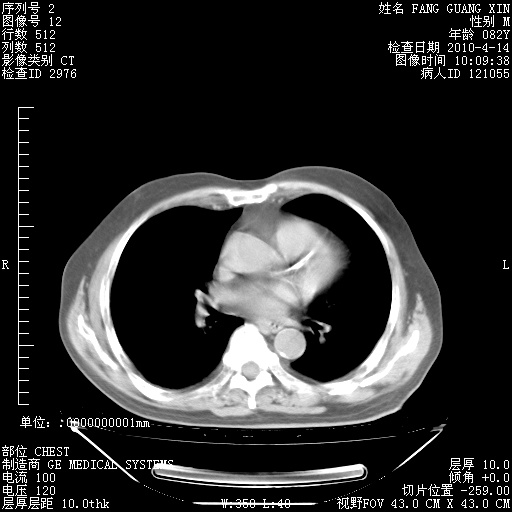

肺部CT平扫未见异常。